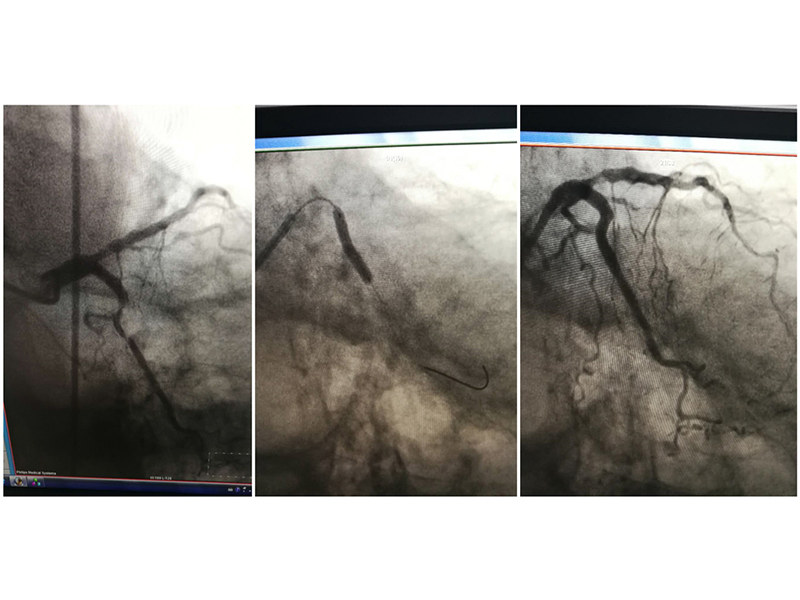

72 5 CTA 4 10